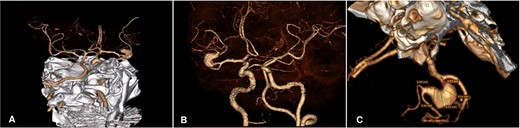

A 46-year-old male with a past medical history of arterial hypertension presented with a 4-month history of recurrent and sporadic headaches, transient ischemic stroke, and a recent 3-day course of left hemiparesis. Neurological examination showed mild 4/5 left-sided hemiparesis and a Glasgow coma scale (GCS) score of 15. A subsequent cerebral angiotomography revealed an unruptured 25 × 10 mm fusiform aneurysm in the superior M2 segment of the MCA (Fig. 1). After discussing potential risks, benefits, and natural history with the patient, we decided to perform a superficial temporal artery (STA) to M3 bypass with proximal occlusion of the giant fusiform aneurysm.

Cerebral Angiotomography. (A) Posterior view depicts an unruptured giant fusiform aneurysm in the M2 segment of the right MCA; (B) Anterior view reveals a close aneurysm proximity to the M1 segment of 3 mm; (C) Complex architecture of the giant fusiform aneurysm is shown with adjacent M2 and M3 branches. MCA: middle cerebral artery